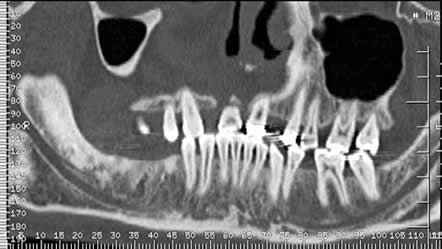

Después de colocado el implante, la oseointegración requiere de al menos 3 meses en la mandíbula y 6 meses en el maxilar. (12). (Fig 32).

Aunque su valoración es principalmente clínica, la radiología puede aportar información adicional. La radiolucencia alrededor del-implante y la pérdida de altura del hueso, de más de un tercio de la longitud del implante o más de 2 mm en cinco años se han postulado como signos de fracaso del implante. (8). (Fig 33 A, B y C).

Fig 32. Seguimiento de implantes.

A y B: TAC reconstrucción sagital. Implantes mandibulares, con adecuada óseo-integración.